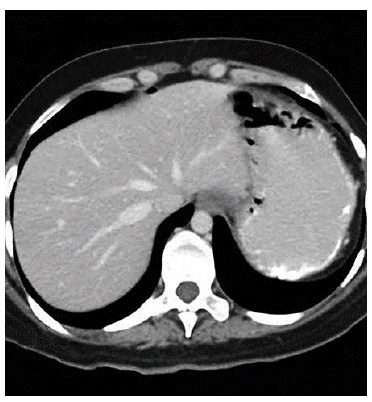

Taking the patient's stability and absence of peritoneal irritation into account, we chose a conservative approach and started intravenous fluid therapy, analgesics, gastric protection, antibiotics (piperacillintazobactam). Abdominal CT showed alteration of mesenteric fat tissue around the distal third of the descending colon and the proximal sigmoid, as well as adjacent air levels indicating pneumoperitoneum around the left hepatic lobe and para-colic mesenteric air (Figures 3 and 4).